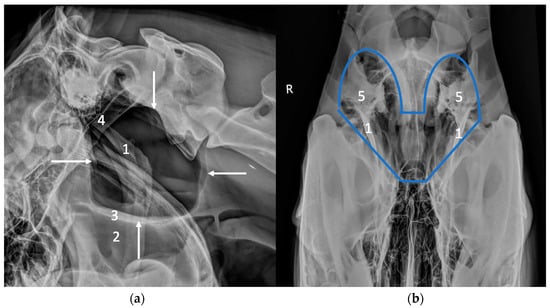

2.1. Radiography